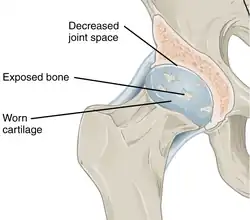

With osteoarthritis, the cartilage becomes worn away. Spurs grow out from the edge of the bone, and synovial fluid increases. Altogether, the joint feels stiff and sore. -

Other structures within the joint can also be affected.[45] The ligaments within the joint become thickened and fibrotic, and the menisci can become damaged and wear away.[46] Menisci can be completely absent by the time a person undergoes a joint replacement. New bone outgrowths, called "spurs" or osteophytes, can form on the margins of the joints, possibly in an attempt to improve the congruence of the articular cartilage surfaces in the absence of the menisci. The subchondral bone volume increases and becomes less mineralized (hypo mineralization).[47] All these changes can cause problems functioning. The pain in an osteoarthritic joint has been related to thickened synovium[48] and to subchondral bone lesions.[49]